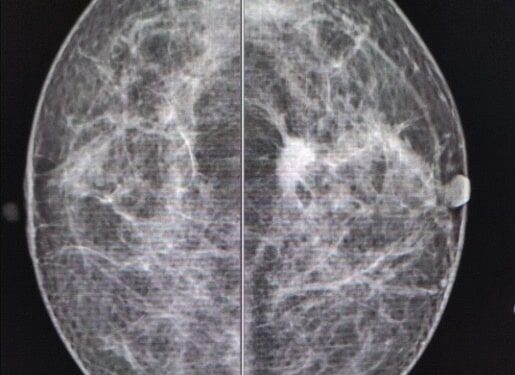

La mastografía en mujeres entre 40 y 69 años.